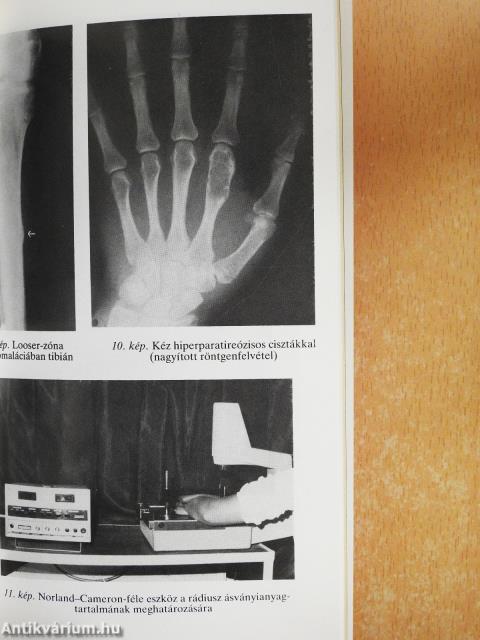

| Radiológiai módszerek | 50 |

| Röntgenfelvétel | 50 |

| A kalcipéniás oszteopátiák kimutatása speciális röntgeneljárásokkal | 54 |

| A mellékpajzsmirigy eredetű csontbetegség és hiperparatireózis | 87 |

| Primer hiperparatireózis | 87 |

| Oszteomalácia | 150 |

| Klinikai kép, röntgenelváltozások | 158 |